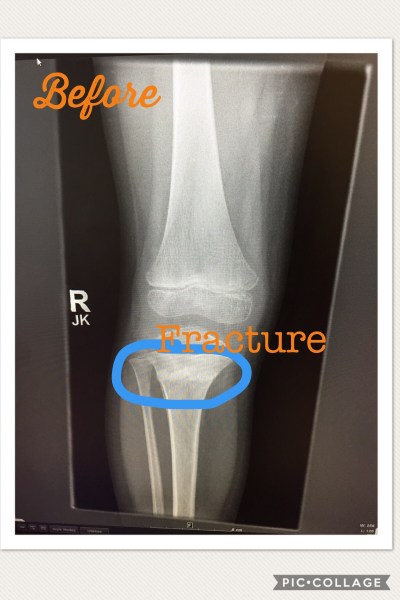

So there’s the fracture, I actually think this was when his cast came off. I’ve tried to repress all memories of when I had two kids in full leg casts

Now that you’ve had a good laugh, the story continues. Well when we went to get him officially casted by the orthopedic physicians assistant, she mentioned that based on the x-rays his pediatrician took, they couldn’t tell if the fracture impacted his growth spurt, I immediately went to leg length differences, surgery and since we were just barely pain free from Sporty’s surgery I couldn’t even process another surgery let alone on the kid who gets a paper cut and acts like the world is coming to an end. (Seriously, he tripped on the sidewalk this week and skinned his arm and for 3 hours he asked why (in the whiniest voice imaginable) they had to make sidewalks so hard!?! Again, can’t make this stuff up!).